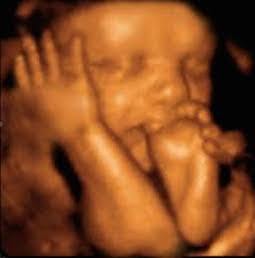

EL DIOS ABORTO

La ideología, el fanatismo y la idolatría a lo que a todas luces es un retroceso, el aborto, quiso anteponerse al buen hacer, al criterio médico. Y el resultado ya se ha visto: muerte de un inocente y daño a una menor que tuvo que ser sometida a un parto para que su hija pudiera morir.

Si dejamos a un lado la ideología, el aborto tiene perdida la batalla. Lo hemos visto en infinidad de ocasiones, y lo seguiremos viendo, no hay marcha atrás. Cada vez son más los avances técnicos, científicos y médicos que ponen en evidencia el fanatismo de la ideología abortista, como ha ocurrido recientemente en Jujuy, en donde lo que se ha buscado por parte de los proaborto no ha sido el bien de la menor, ni protegerla de futuras secuelas psicológicas, ni cuidar de su intimidad o de su salud física. El objetivo de ese colectivo era que el aborto, al que rinden culto como si de un dios se tratara, fuera el vencedor. Lo demás daba igual, pero el aborto tenía que hacerse sí o sí.

Claro como el agua. La ideología, el fanatismo y la idolatría a lo que a todas luces es un retroceso, el aborto, quiso anteponerse al buen hacer, al criterio médico, a la profesionalidad de un equipo que no tienen más interés que servir al ser humano. Y el resultado ya se ha visto: muerte de un inocente y daño a una menor que tuvo que ser sometida a un parto para que su hija pudiera morir “con todas las de la ley”

Qué paradoja, provocar un parto prematuro para asegurarse de que el recién nacido muera, evitar esperar dos semanas porque entonces podría haber sobrevivido, y eso, nunca.

Por desgracia aún nos quedan muchas cosas por ver, pero las voces cada vez son más y más autorizadas, como la del Dr. Briones que ha sido incapaz de permanecer a las órdenes de quien no sabe nada de Medicina y mucho de sectarismo. Sólo anclándose en el pasado y en la mentira se puede seguir reivindicando el aborto, como ha ocurrido esta semana en Nueva York. Las imágenes hablan por sí solas: la abogada mentirosa que se inventó el caso de Norma McCorvey y que sirvió para que se legalizara el aborto en Estado Unidos en la sentencia Roe vs Wade, sentada junto a un gobernador obsesionado con el aborto, y con un grupo de personajes siniestros que reían a carcajadas mientras se firmaba lo que hoy, en pleno siglo XXI, es un retroceso ante el avance imparable de la evidencia científica: la vida del hijo en el seno materno es una realidad innegable, las personas con síndrome de Down son iguales que el resto, y la diferencia, la enfermedad y las condiciones físicas de cada cual no pueden ser motivo de discriminación.

El nombre de la niña que luchó por vivir y no pudo nos animará a seguir en la causa: Esperanza.